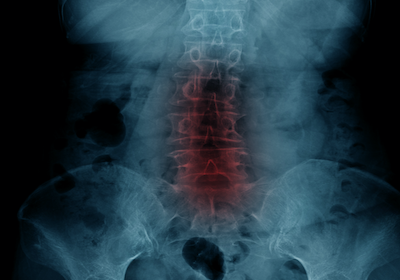

sciatic nerve pain

The sciatic nerve runs from your lower back, via the buttock and down the back of the thigh and leg to the foot.

It can get irritated, inflamed, or squashed anywhere along its path and become a cause of pain.

This is known as sciatica.